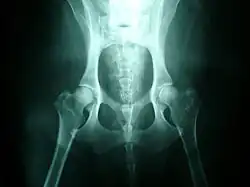

Klasický diagnostický postup využívá rentgenových snímků a bodovacího testu kyčlí. Provádí se v odpovídajícím věku a je vhodné ho zopakovat ještě v dospělosti (pokud se test udělá příliš brzy, jsou výsledky neprůkazné). Protože dysplazie je do velké míry dědičná, doporučuje se zkontrolovat stupeň dysplazie u rodičů před koupí štěněte a také při posuzování vhodnosti psa pro chov. Ale přestože je tato porucha dědičná, může se objevit i u psů, jejichž rodiče mají stupeň dysplazie negativní.

Existuje několik různých systémů pro posuzování stupně dysplazie, zpravidla však vedou k rozdělení do pěti kategorií: A – negativní, B – hraniční, C – mírná dysplazie, D – střední dysplazie, E – těžká dysplazie. Pro pořízení korektních snímků je nutná sedace zvířete, aby bylo možné ho udržet v klidu ve správné poloze a aby se snížil svalový tonus.